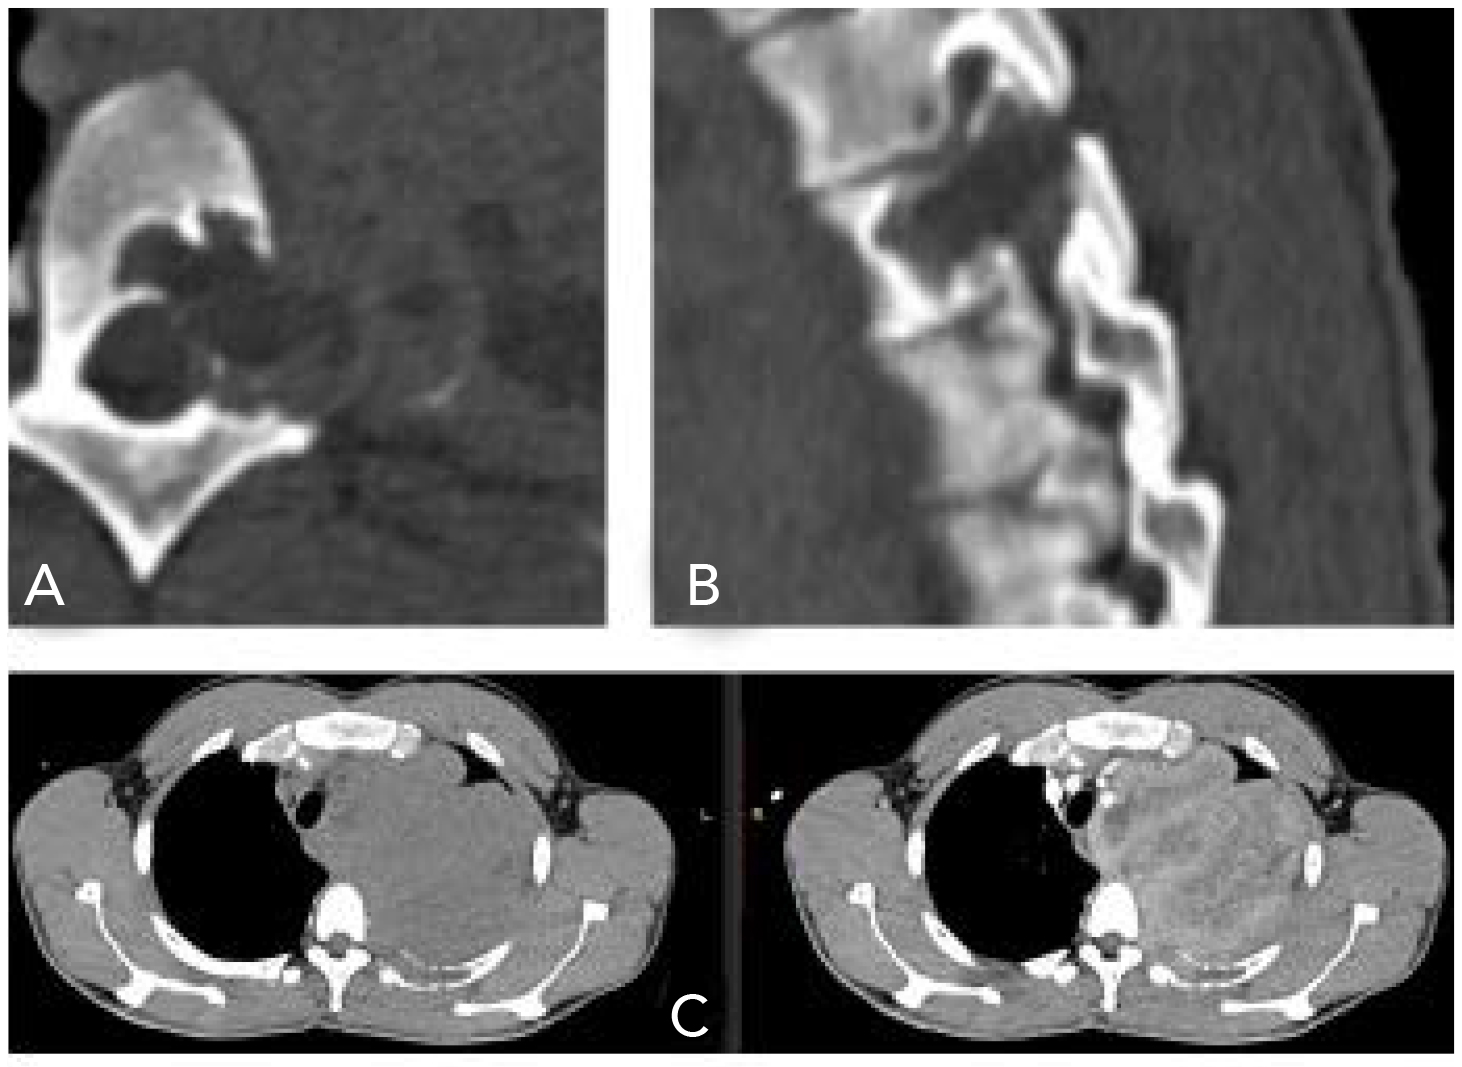

En el corte axial y sagital se observó una lesión ósea lítica, con bordes geográficos que afectaban el pedículo, parte del cuerpo y de la apófisis transversa de la vértebra T4, así como la parte posterior del cuarto arco costal izquierdo. Dicha lesión se extendía en sentido caudal y se introducía al foramen de T3-T4 y T4-T5 (figuras 4A y 4B). Al hacer contacto con la duramadre, condicionaba el desplazamiento de la arteria y la vena subclavias, pero no las comprimía.

Figura 4. A) Corte axial a la altura de T4. B) Corte sagital T3-T5. C) Reconstrucción de corte transversal a la altura de T3